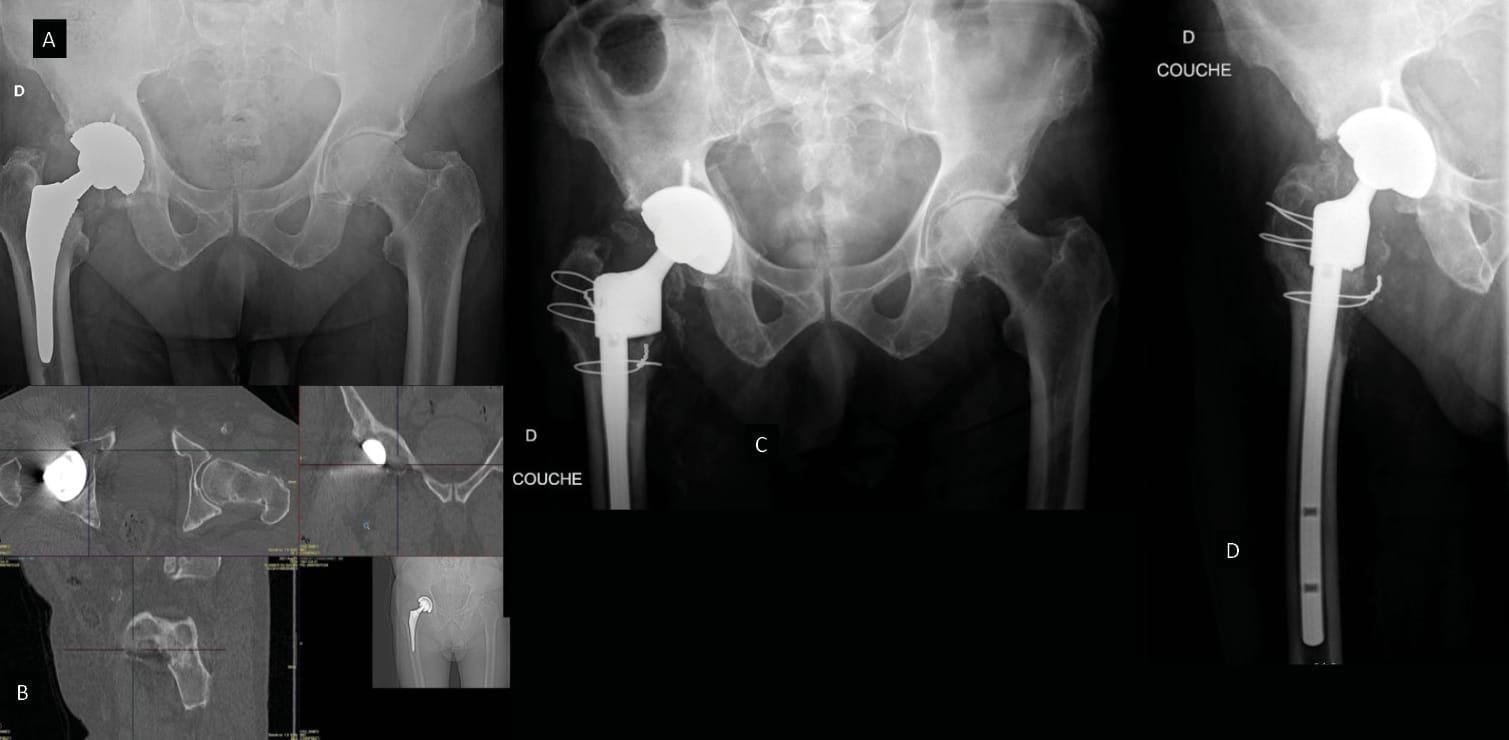

DM cup cemented into an existing osteointegrated cup

One of the options could be to cement a DM cup into an existing metal acetabular component that is securely fixed. This presents a simple alternative to conventional revision of a securely fixed and well positioned acetabular component that can shorten operations and reduce blood loss, bone damage and overall perioperative morbidity. Wegrzyn et al. [44] Wegrzyn J, Saugy C-A, Guyen O, Antoniadis A. Cementation of a Dual Mobility Cup Into an Existing Well-Fixed Metal Shell: A Reliable Option to Manage Wear-Related Recurrent Dislocation in Patients With High Surgical Risk. J Arthroplasty 2020;35:2561–6. https://doi.org/10.1016/j.arth.2020.05.001. showed that a dual mobility acetabular component cemented into a securely fixed metal cup could be a biomechanically acceptable alternative [53] Wegrzyn J, Thoreson AR, Guyen O, Lewallen DG, An K-N. Cementation of a dual-mobility acetabular component into a well-fixed metal shell during revision total hip arthroplasty: A biomechanical validation. J Orthop Res 2013;31:991–7. https://doi.org/10.1002/jor.22314.. They reported significant improvement of function in a case series of 28 patients with a mean follow-up of 3.5 years (2–5) and they emphasised the advantages in terms of operating time (107 minutes; 75–140), perioperative bleeding, and an absence of complications, repeat surgery or revision during follow-up.

In conclusion, this strategy involves a simple revision technique that reduces blood loss, effectively restores stability and delivers a secure acetabular construction in frail patients who present a high surgical risk and/or are older than their natural life expectancy. Ciolli et al. carried out a literature review, and, with 1– 4 years of follow-up, reported survival curves ranging from 85 to 100% 19, which suggests that this alternative, although it should be reserved for a target group, appears to be viable.

Looking at the treatment of Paprosky grade 3B massive acetabular defects, Di Laura et al. [68] Di Laura A, Henckel J, Hart A. Custom 3D-Printed Implants for Acetabular Reconstruction: Intermediate-Term Functional and Radiographic Results. JBJS Open Access 2023;8. https://doi.org/10.2106/JBJS.OA.22.00120. analysed the results after a minimum of 3 years of use of 3D printed ProMade implants, with a dual mobility bearing incorporated into the device in all cases. This study suggested that these acetabular implants are a good option to treat these types of defects with a cumulative survival rate of 100%, significant improvements on pain and function rating scales and excellent osteointegration. The accuracy and feasibility of surgical planning, assessed by observing implant positioning and orientation on a postoperative CT scan, shows that this strategy can be trusted [69] Durand-Hill M, Henckel J, Di Laura A, Hart AJ. Can custom 3D printed implants successfully reconstruct massive acetabular defects? A 3D-CT assessment. J Orthop Res 2020;38:2640–8. https://doi.org/10.1002/jor.24752.. One way in which it contributes to improving function for patients is by addressing leg length discrepancy, which can often be an issue in revisions when there is significant bone loss [70] Di Laura A, Henckel J, Dal Gal E, Monem M, Moralidou M, Hart AJ. Reconstruction of acetabular defects greater than Paprosky type 3B: the importance of functional imaging. BMC Musculoskelet Disord 2021;22:207. https://doi.org/10.1186/s12891-021-04072-4.. An example of planning with a custom-made implant is shown in figure 9.